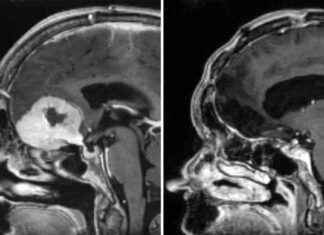

Innovative Brain Tumour Removal Through Eyebrows: A Breakthrough Surgery

A surgeon in Aberdeen, Anastasios Giamouriadis, has made a groundbreaking discovery in brain tumor removal. By adapting an existing technique, he can now remove large tumors through patients' eyebrows, leaving them with minimal scarring...